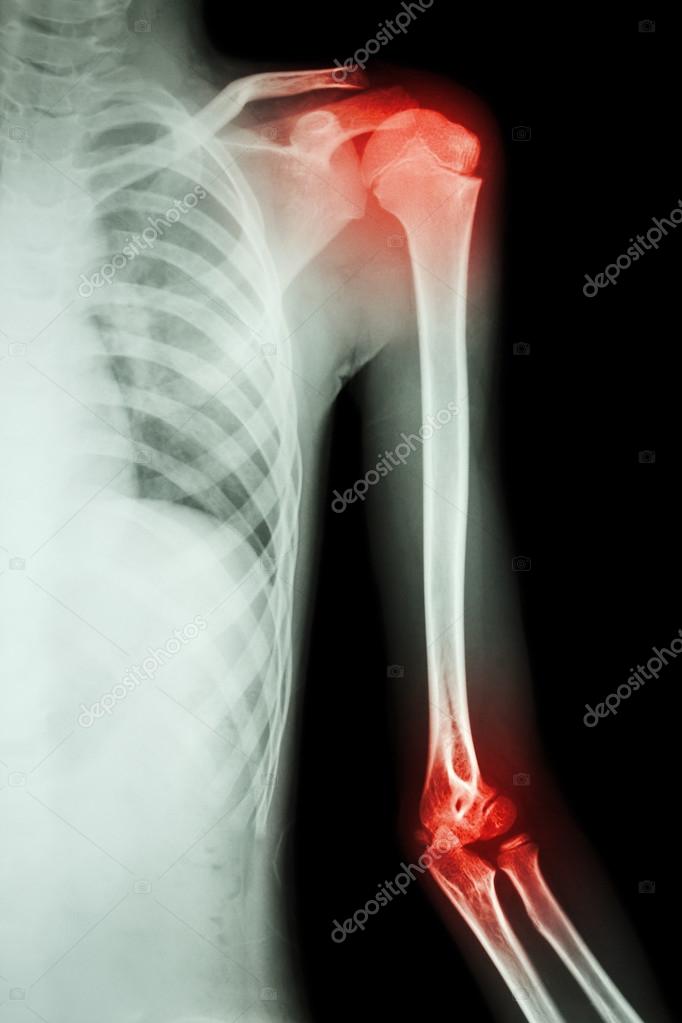

Shoulder X Ray Showing Arthritis . Symptoms include pain, stiffness, decreased. Healthy joints have a clear, even space. Symptoms of shoulder arthritis may include pain in the shoulder joint, stiffness and reduced range of motion. Shoulder arthritis symptoms include persistent pain, stiffness, limited range of motion, weakness, and a grinding or clicking sensation in the joint, which, if left untreated, could. Shoulder arthritis is inflammation in your shoulder joint. Over time, arthritis leads to cartilage loss. They can help distinguish among various forms. Healthcare providers use a shoulder x. There are many nonoperative treatments for shoulder arthritis, including. The upper end of the. The shoulder is made up of a number or interconnected bones.

From depositphotos.com

Left shoulder x ray anatomy Film xray left shoulder and arthritis at Shoulder X Ray Showing Arthritis The shoulder is made up of a number or interconnected bones. There are many nonoperative treatments for shoulder arthritis, including. Healthcare providers use a shoulder x. They can help distinguish among various forms. The upper end of the. Over time, arthritis leads to cartilage loss. Shoulder arthritis is inflammation in your shoulder joint. Symptoms of shoulder arthritis may include pain. Shoulder X Ray Showing Arthritis.